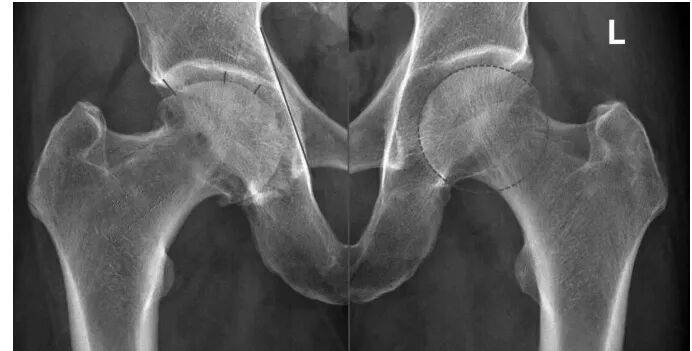

仔细看MRI片(图1),可见左侧股骨头(L)很圆,右侧股骨头不仅不圆且髋臼有内陷。将MRI片与CT片(图2)结合起来,可以明确诊断。CT片可见关节面下囊性变,关节间隙不等宽,周围还有骨质增生。